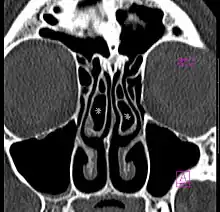

Concha bullosa on both sides (marked with asterisks), coronal orientated image from CT

A concha bullosa is a pneumatized (air-filled) cavity within a nasal concha, also known as a turbinate.[1] Bullosa refers to the air-filled cavity within the turbinate.[1] It is a normal anatomic variant seen in up to half the population. Occasionally, a large concha bullosa may cause it to bulge sufficiently to obstruct the opening of an adjacent sinus, possibly leading to recurrent sinusitis[1] and various head pains related to areas innervated by the trigeminal nerve.[2] In such a case the turbinate can be reduced in size by endoscopic nasal surgery (turbinectomy). The presence of a concha bullosa is often associated with deviation of the nasal septum toward the opposite side of the nasal cavity.[3]